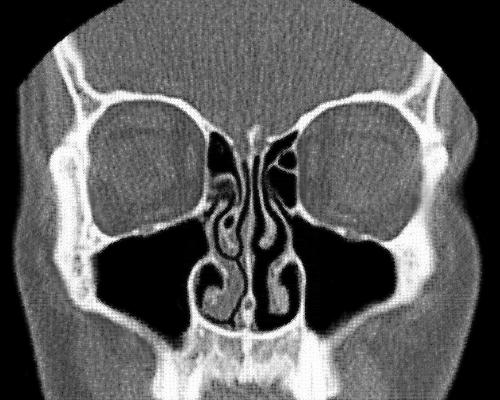

В любой момент времени одна ноздря является ведущей (рабочей), пропуская через себя основной поток воздуха. Вторая в это время переходит в режим отдыха: её ткани набухают, сужая проход и снижая поток воздуха до минимума. Это позволяет слизистой восстановить уровень влаги и накопить тепло. Спустя несколько часов (обычно от 2 до 4) происходит пересменка. Ведущая ноздря уходит на покой, а отдохнувшая берет нагрузку на себя.